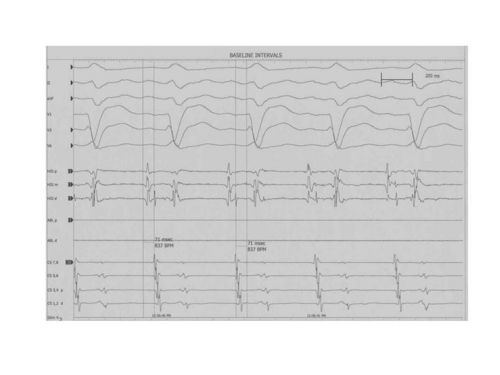

During SVT if you perform the Ventricular Overdrive Maneuver which is pacing at a Cycle Length 10 to 60 msec shorter than the tachycardia Cycle Length until 1:1 VA conduction. Once you stop pacing if you look at the reponse you will see a VAV response or a VAAV (VAAH) response which indicates Atrial Tachycardia